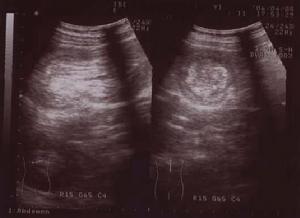

腸套疊檢查2、B超檢查顯示腸套疊包塊。